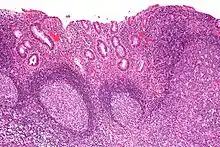

| Micrograph showing colonic-type mucosa with follicular lymphoid hyperplasia, as is seen in diversion colitis. H&E stain. | |

Diversion colitis is an inflammation of the colon which can occur as a complication of ileostomy or colostomy, where symptoms may occur between one month and three years following surgery.[1] It also occurs frequently in a neovagina created by colovaginoplasty, with varying delay after the original procedure.[2] Despite the presence of a variable degree of inflammation the most suggestive histological feature remains the prominent lymphoid aggregates.